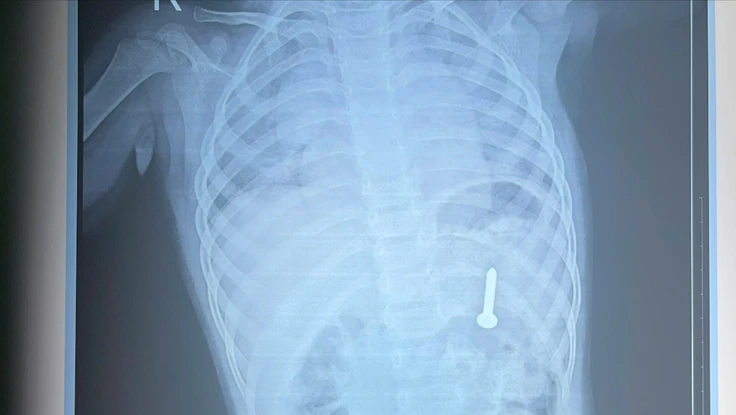

(PLO)- Nam bệnh nhân có tiền sử rối loạn tâm thần tự nuốt 3 bàn chải đánh răng dài gần 20 cm đã được các bác sĩ Bệnh viện Trung ương Huế nội soi, gắp dị vật ra ngoài an toàn.